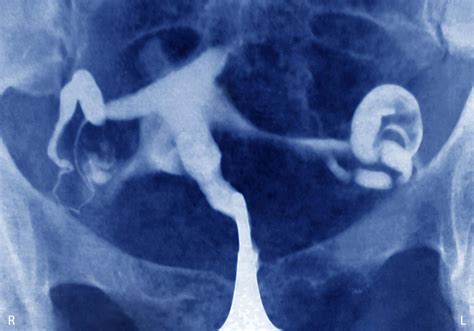

Discovering that you are experiencing an ectopic pregnancy can be an emotionally and physically overwhelming experience. When a fertilized egg implants outside the uterus—most commonly in the fallopian tube—it cannot develop normally and poses a significant health risk to the individual. In many early-detected cases, methotrexate for ectopic pregnancy serves as a highly effective, non-surgical treatment option. This medication works by stopping the growth of the rapidly dividing cells that make up the pregnancy tissue, allowing the body to naturally absorb the tissue over time.

An ectopic pregnancy is a medical emergency that requires timely intervention. When caught early, before the tube has ruptured, doctors often recommend medication rather than surgery to resolve the condition. Methotrexate for ectopic treatment is a folate antagonist. By interfering with the body's use of folic acid, the drug effectively stops the development of the pregnancy, which is composed of rapidly growing cells that require high levels of folate.

• The ectopic mass is typically measured to be smaller than 3.5 to 4 centimeters.